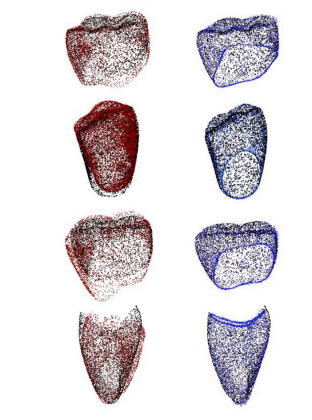

Fig. 4. Comparison of predicted point clouds using our proposed method with previouswork. (𝑎) Illustrates the predicted point cloud using the method by Hosseinimaneshet al. (2023b) with 1536 points. (𝑏) Depicts the same method by Hosseinimanesh et al.(2023b), but with a higher resolution of 3072 points, resulting in a noisier output. (𝑐)Displays the prediction using our proposed model, and (𝑑) represents the ground truth,with both (𝑐) and (𝑑) at the sameresolution of 3072 points

图4:使用我们提出的方法所预测的点云与先前研究成果的比较。(a)展示了使用侯赛尼马内什等人(2023b)的方法预测出的具有1536个点的点云。(b)描绘的是侯赛尼马内什等人(2023b)的相同方法,但分辨率更高,为3072个点,其输出结果包含更多噪声。(c)显示的是使用我们所提出模型的预测结果,(d)代表真实值,(c)和(d)的分辨率相同,均为3072个点。

Fig. 5. Visual comparison of dental crown predictions: Predictions from the FSC model(left column) and AdaPoinTr model (right column) are shown for four cases. In eachvisualization, black points represent the ground truth, red points indicate predictionsby the FSC model, and blue points correspond to predictions by AdaPoinTr model.As depicted, the blue points from AdaPoinTr model consistently align closely with theblack ground truth points, while red points from the FSC model exhibit noticeabledeviations, indicating a lower accuracy in shape completion compared to AdaPoinTrapproach.

图5:牙冠预测的可视化比较:展示了四种情况下来自FSC模型(左列)和AdaPoinTr模型(右列)的预测结果。在每次可视化中,黑色点代表真实值,红色点表示FSC模型的预测结果,蓝色点对应AdaPoinTr模型的预测结果。如图所示,AdaPoinTr模型的蓝色点始终与黑色的真实值点紧密对齐,而FSC模型的红色点则表现出明显的偏差,这表明与AdaPoinTr方法相比,FSC模型在形状补全方面的准确性较低。